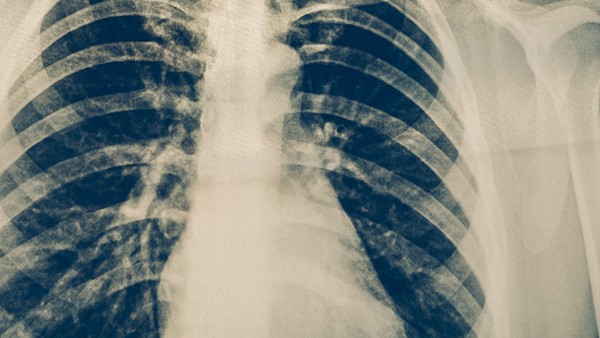

1.定义不同:肺门结核是指发生在肺门淋巴结的结核病。而肺结核是一种由结核分支杆菌感染引起的慢性呼吸系统传染病。

3.症状不同:肺门结核患者通常会出现咳嗽、咳痰、发热等症状,并且还会伴有食欲不振、盗汗等现象。而肺结核的症状则会比较严重,除了上述症状以外,还可能会出现咯血、胸痛等不适症状。